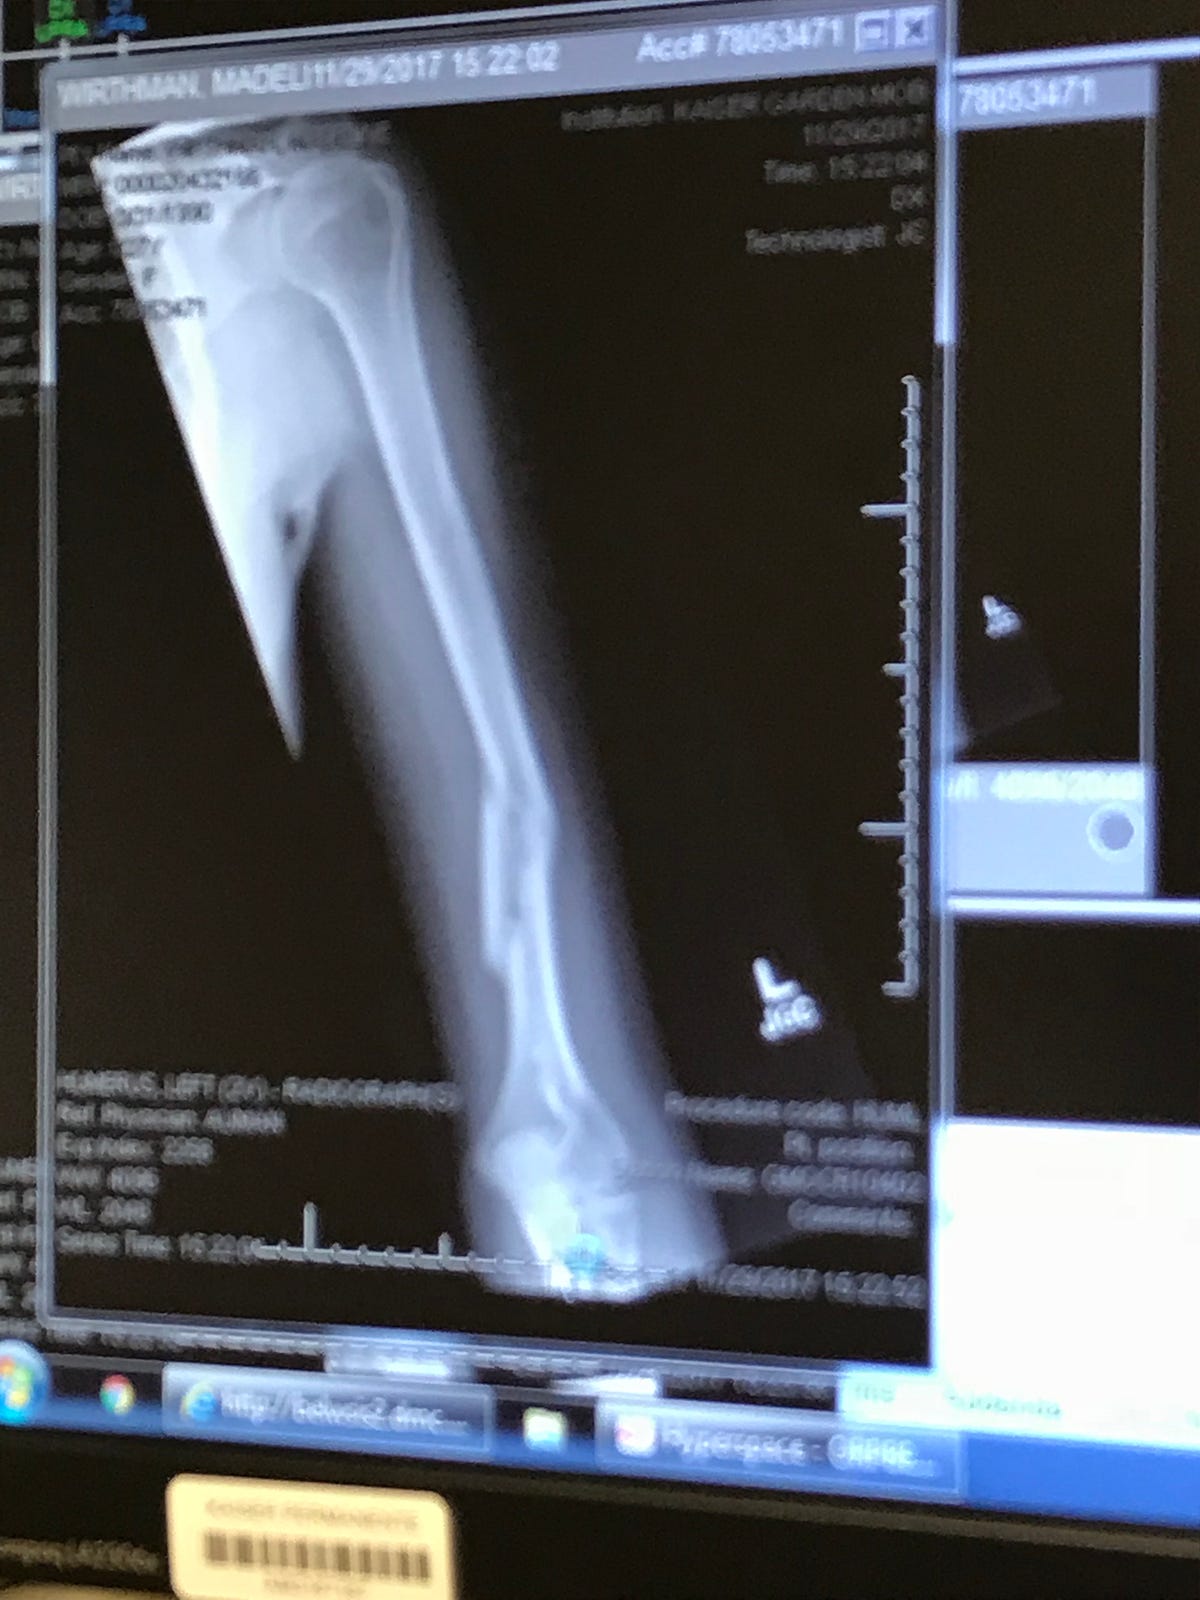

From medium.com

A Broken Humerus — Road to Recovery Maddie Wirthman Medium How To Heal A Broken Humerus The humerus is the long bone in your upper arm. It takes three to four months for the bone to heal. Some people can recover without surgery and only need a. A temporary splint extending from the shoulder to the forearm and holding the elbow bent at 90 degrees can be used for initial management of the fracture. a. How To Heal A Broken Humerus.

A Broken Humerus — Road to Recovery Maddie Wirthman Medium How To Heal A Broken Humerus It is important to remember that a shoulder fracture is a significant injury. the humerus is the upper arm’s only bone. A fracture of the proximal part means that it is broken up near the shoulder joint. These fractures normally take between 6 to 12 weeks to heal. As healing progresses, more aggressive shoulder strengthening exercises can resume, and. How To Heal A Broken Humerus.

A Broken Humerus — Road to Recovery by Maddie Wirthman Medium How To Heal A Broken Humerus the humerus is the upper arm’s only bone. A fracture of the proximal part means that it is broken up near the shoulder joint. It is important to remember that a shoulder fracture is a significant injury. It connects the shoulder to the elbow and is strong enough that breaking it typically requires. Most broken shoulders can be treated. How To Heal A Broken Humerus.

A Broken Humerus — Road to Recovery by Maddie Wirthman Medium How To Heal A Broken Humerus These fractures normally take between 6 to 12 weeks to heal. How should it be treated? This fracture can be treated in a sling for 4 weeks. It connects the shoulder to the elbow and is strong enough that breaking it typically requires. A temporary splint extending from the shoulder to the forearm and holding the elbow bent at 90. How To Heal A Broken Humerus.

A Broken Humerus — Road to Recovery Maddie Wirthman Medium How To Heal A Broken Humerus These fractures normally take between 6 to 12 weeks to heal. This fracture can be treated in a sling for 4 weeks. The humerus is the long bone in your upper arm. what is a proximal humerus fracture? a humerus shaft fracture may be treated with or without surgery, depending on the fracture pattern and associated injuries (i.e.,. How To Heal A Broken Humerus.

A Broken Humerus — Road to Recovery Maddie Wirthman Medium How To Heal A Broken Humerus A fracture of the proximal part means that it is broken up near the shoulder joint. It is important to remember that a shoulder fracture is a significant injury. what is a proximal humerus fracture? the humerus is the upper arm’s only bone. Some people can recover without surgery and only need a. It connects the shoulder to. How To Heal A Broken Humerus.